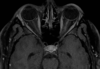

46 anos, pós trauma

Lesão axonal difusa A TC mostra discreta HSA RM T2 \* mostra focos de hemossiderina na transição substância branca e cinzenta, consistentes com LAD. Observe que a localização das microbleeds é diferente dos sangramentos CAA localizados na periferia.